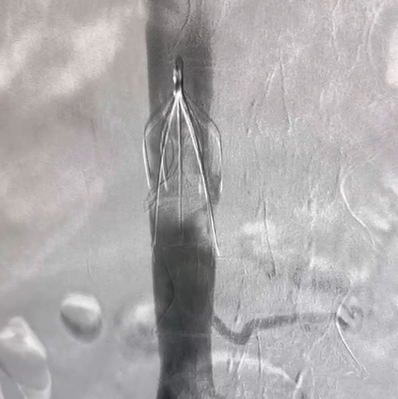

产品介绍

Vewatch®/海神盾™腔静脉滤器通过经股静脉或经颈静脉入路经皮置入,用于预防下腔静脉系统栓子脱落而引起的肺动脉栓塞(PE)。包括:1.已经发生PE或下腔静脉及髂、股、腘静脉血栓形成的患者有下述情况之一者:(1)存在抗凝治疗禁忌证者;(2)抗凝治疗过程中发生出血等并发症;(3)充分的抗凝治疗后仍复发PE和各种原因不能达到充分抗凝者。2.PE,同时存在下肢深静脉血栓形成者。3.髂、股静脉或下腔静脉内有游离漂浮血栓或大量血栓。4.诊断为易栓症且反复发生PE者。5.急性下肢深静脉血栓形成,欲行经导管溶栓和血栓清除者。